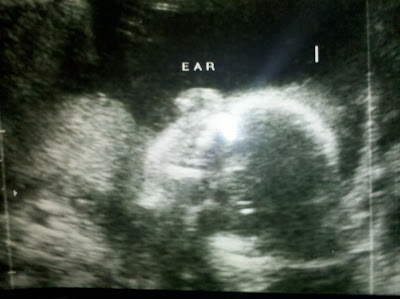

I Think He Is Giving A "Thumbs Up?"

So we went to the Baby Doctor Appointment last night and we are, so far, having a healthy, one pound, baby ??????? So no, we didn't find out what the sex is. I left it entirely up to Jim and he decided not to find out, for now. We have another opportunity in about 10 weeks to "ruin" the surprise, (kidding Jim).

But life is good. We saw the head, heart, toes, arms, legs and a cute little ear. Perfection. The baby is in the 70% percentile. Oh yeah, he/she is already being judged against his/her peers. These kids today don't get off to easy, the race has already begun. So now all to do is eat, pee, walk and wait another 18 or so weeks. I am thinking Memorial Day. That would be a fun birthday...parades, BBQ's, picnics and red, white and blue outfits! FUN! Oh, but wait, that means that I will be in the hospital THIS Memorial Day....hmmm? Perhaps the Friday before, that way I can FINALLY have that beer I have been craving!